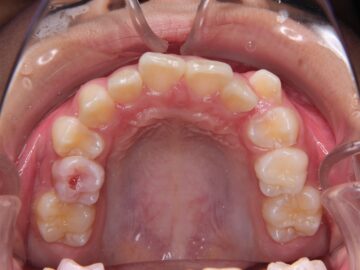

ご相談時

八重歯・歯がガタガタしている